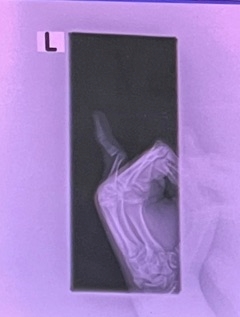

🐣ちゃんの小指が

あらぬ感じで

曲がりました

部活中に

指を脱臼したと

写真が送られてきて

痛そうなの見るの

苦手な方は

ここで戻って下さいね

学校顧問の先生から

電話で

救急が混んでて

2時間は待ち時間かかる

そして

もし待っても

整形外科の先生が

いるか分からないから

その日にはめて

もらえないかもしれないけど

病院連れて行きますか?

結果的に

処置できる先生いたみたいで

麻酔してはめてくれたって

良かった良かった